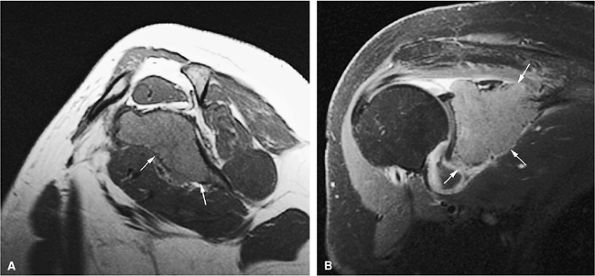

![]() |

FIGURE 13.64 ● Metastatic breast cancer involving the shoulder. (A) Diffuse hypointense marrow replacement is seen on a sagittal T1-weighted image (arrows). (B) Metastatic tumor is better visualized on the coronal STIR image (white arrows). Uninvolved marrow is hypointense (black arrows).